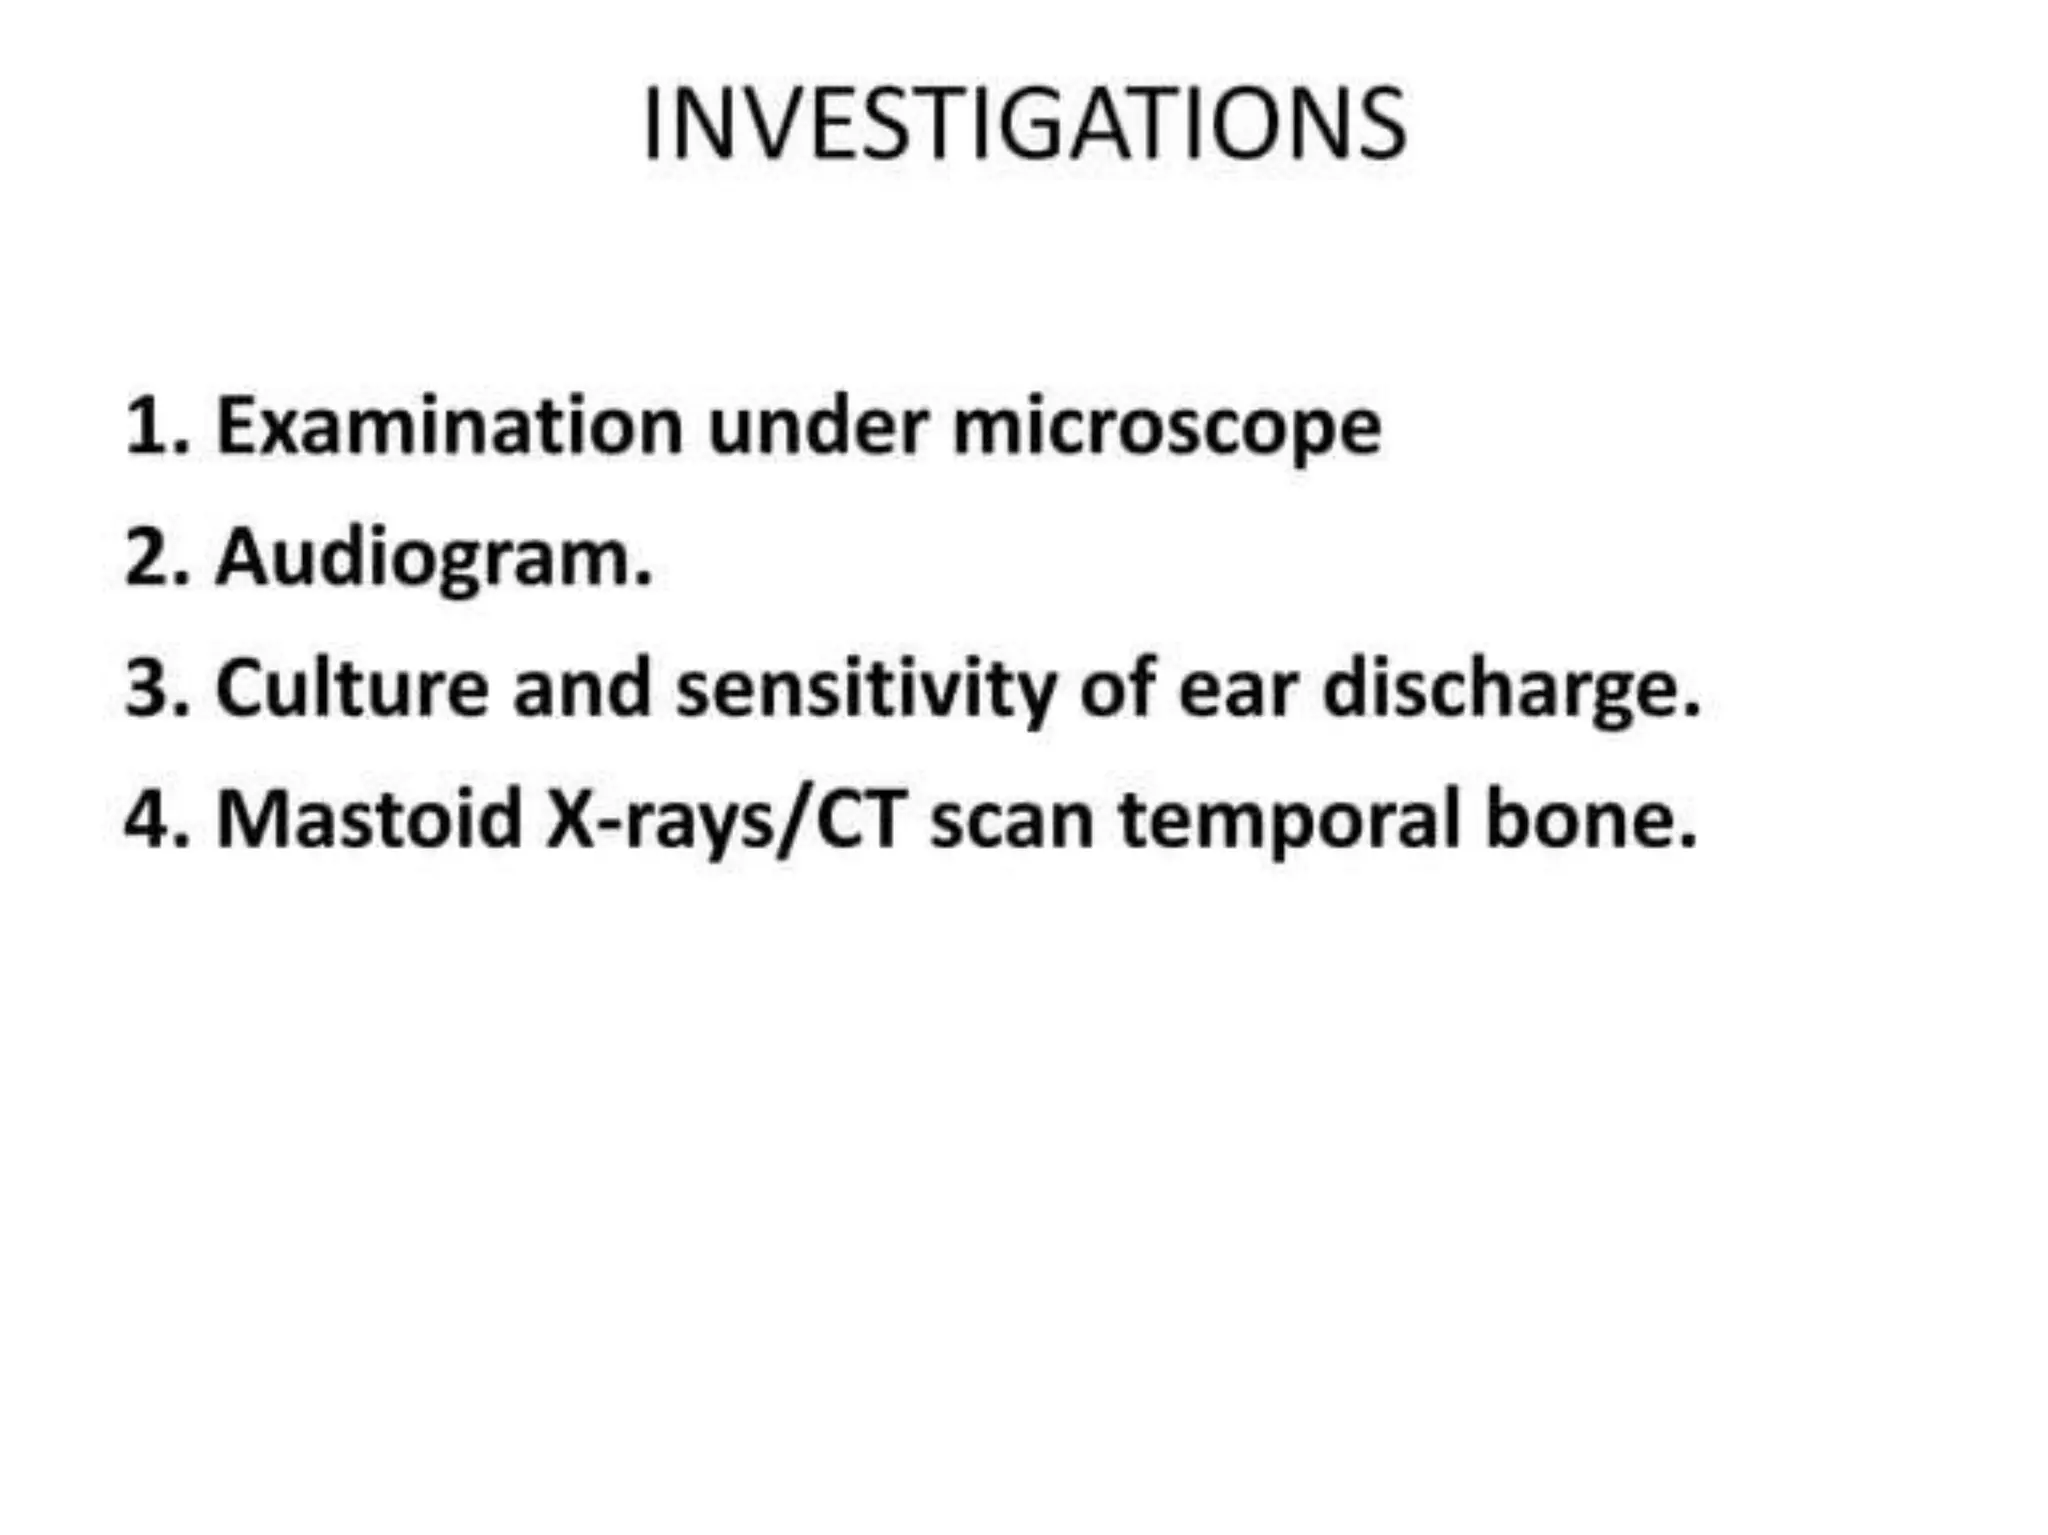

Chronic otitis media is a chronic inflammation of the middle ear and mastoid cavity that presents with recurrent ear discharge through a perforated eardrum. It has several subtypes depending on the state of the eardrum perforation and epithelium. It can be caused by prior acute otitis media, genetics, environment, eustachian tube issues, gastroesophageal reflux disease, craniofacial abnormalities, or immune deficiency.